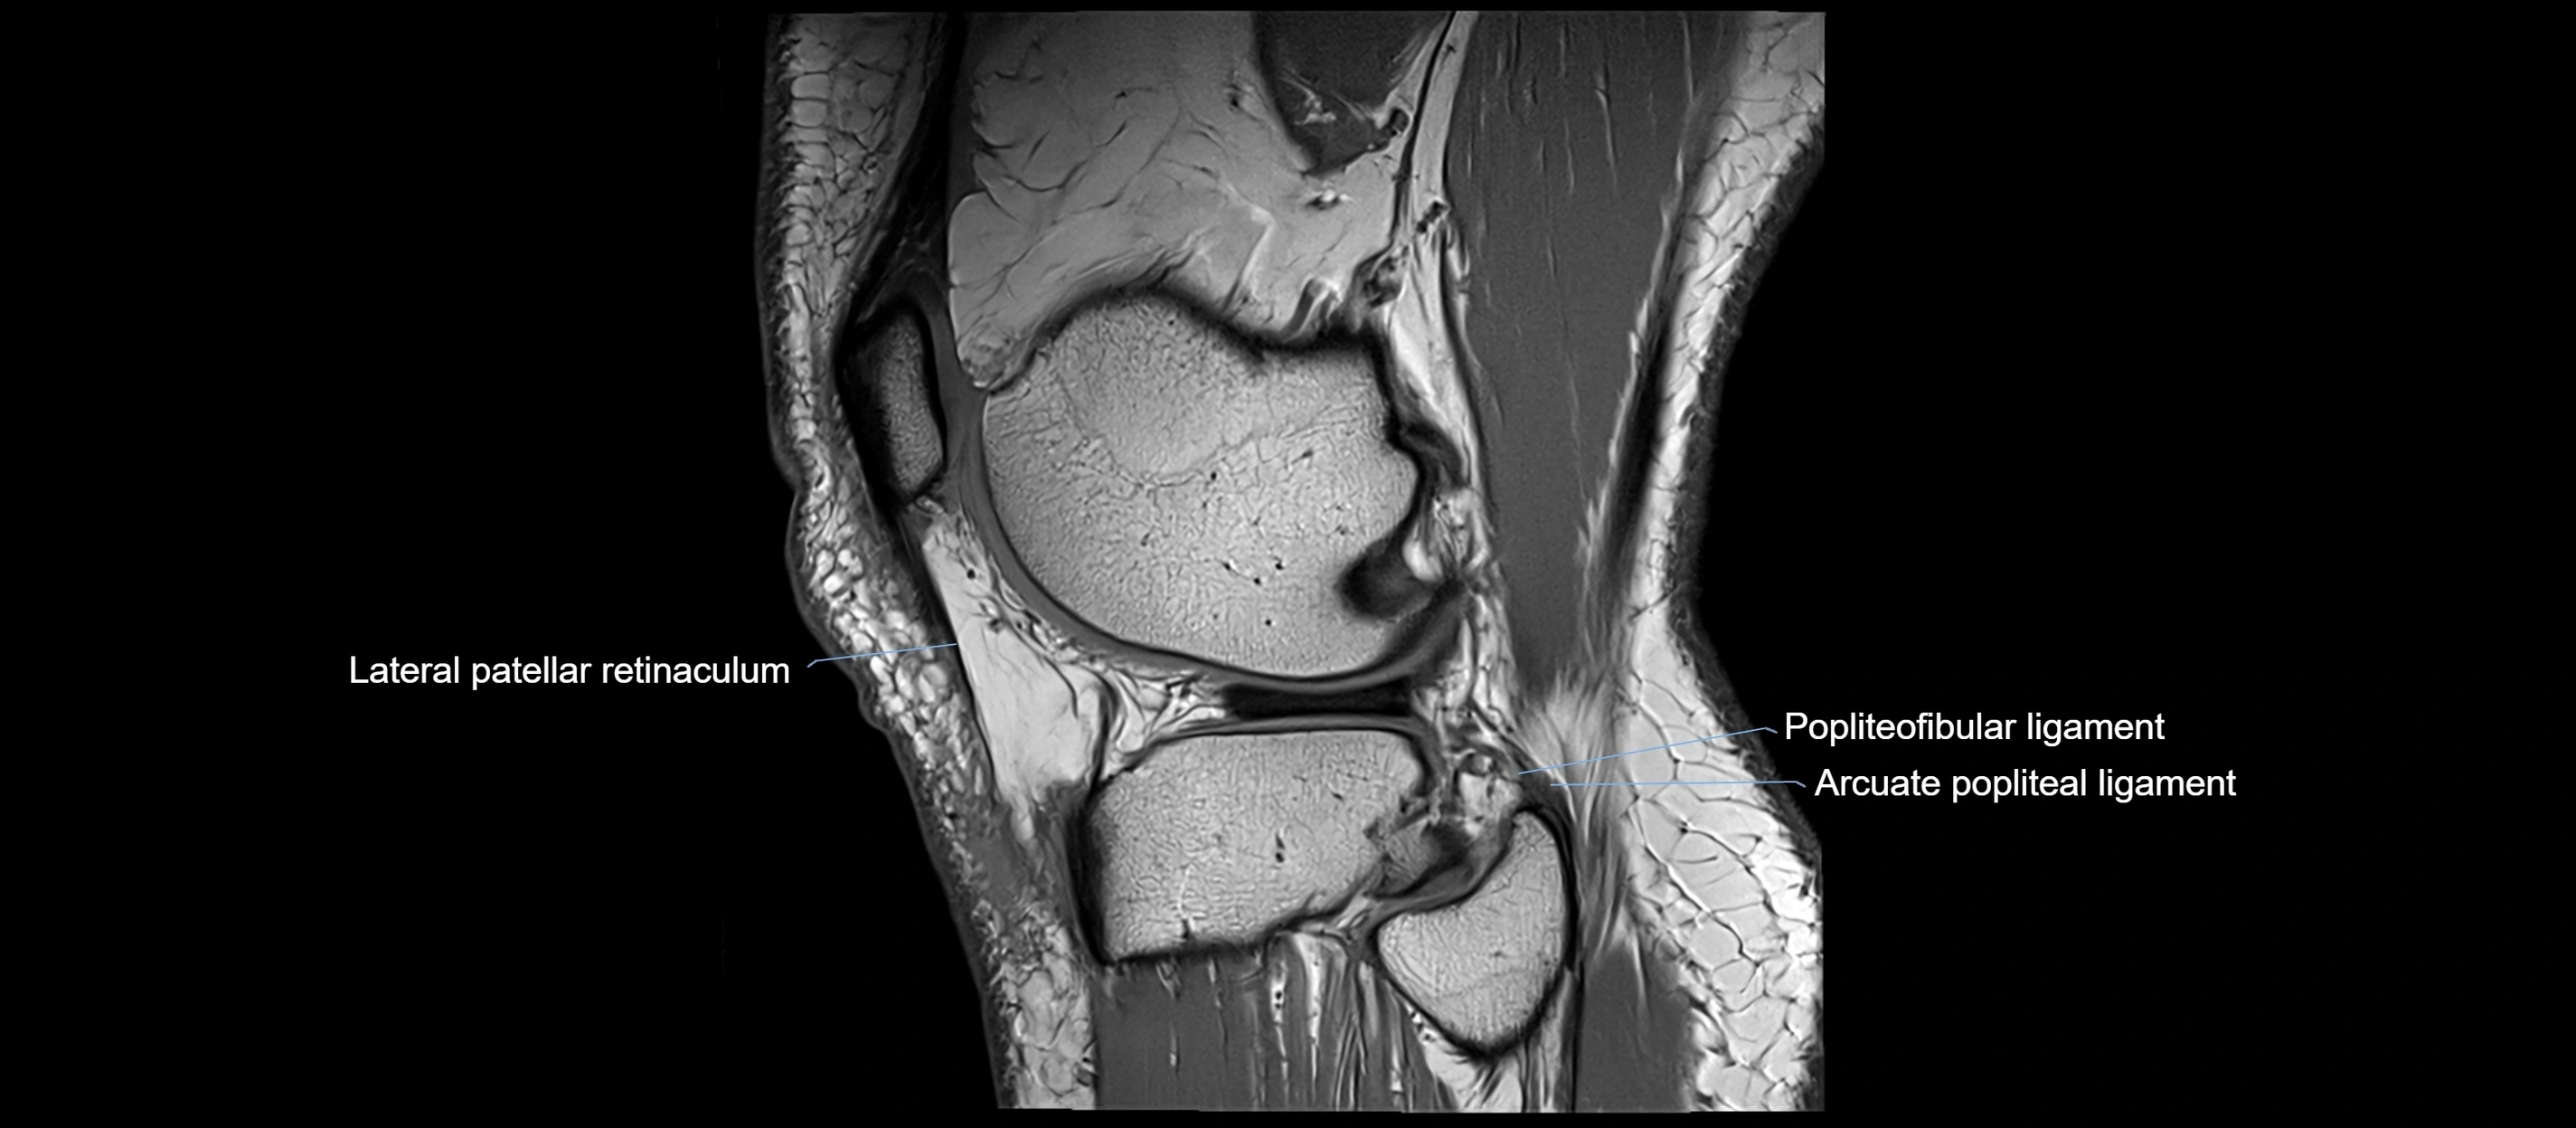

MRI images

image